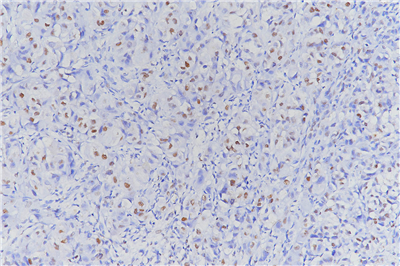

(6)DAB染色3-10min,自来水冲洗,苏木素复染, 1%盐酸酒精分化,显微镜下观察,控制染色程度。

(10)通过显微镜采集分析样本相关部位,计算凋亡率。